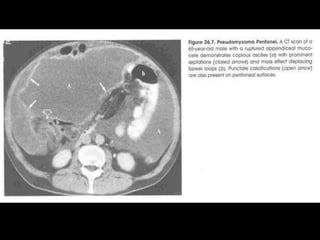

Pseudomyxoma peritonei (PMP) is a rare condition characterized by gelatinous ascites resulting from the rupture of appendiceal mucinous tumors, leading to significant abdominal complications. The incidence is approximately 2 cases per million per year, with a predominance in females, and diagnosis often relies on imaging techniques like ultrasound and CT scans. Effective treatment involves cytoreductive surgery combined with hyperthermic intraperitoneal chemotherapy (HIPEC) to manage disease progression and improve outcomes.